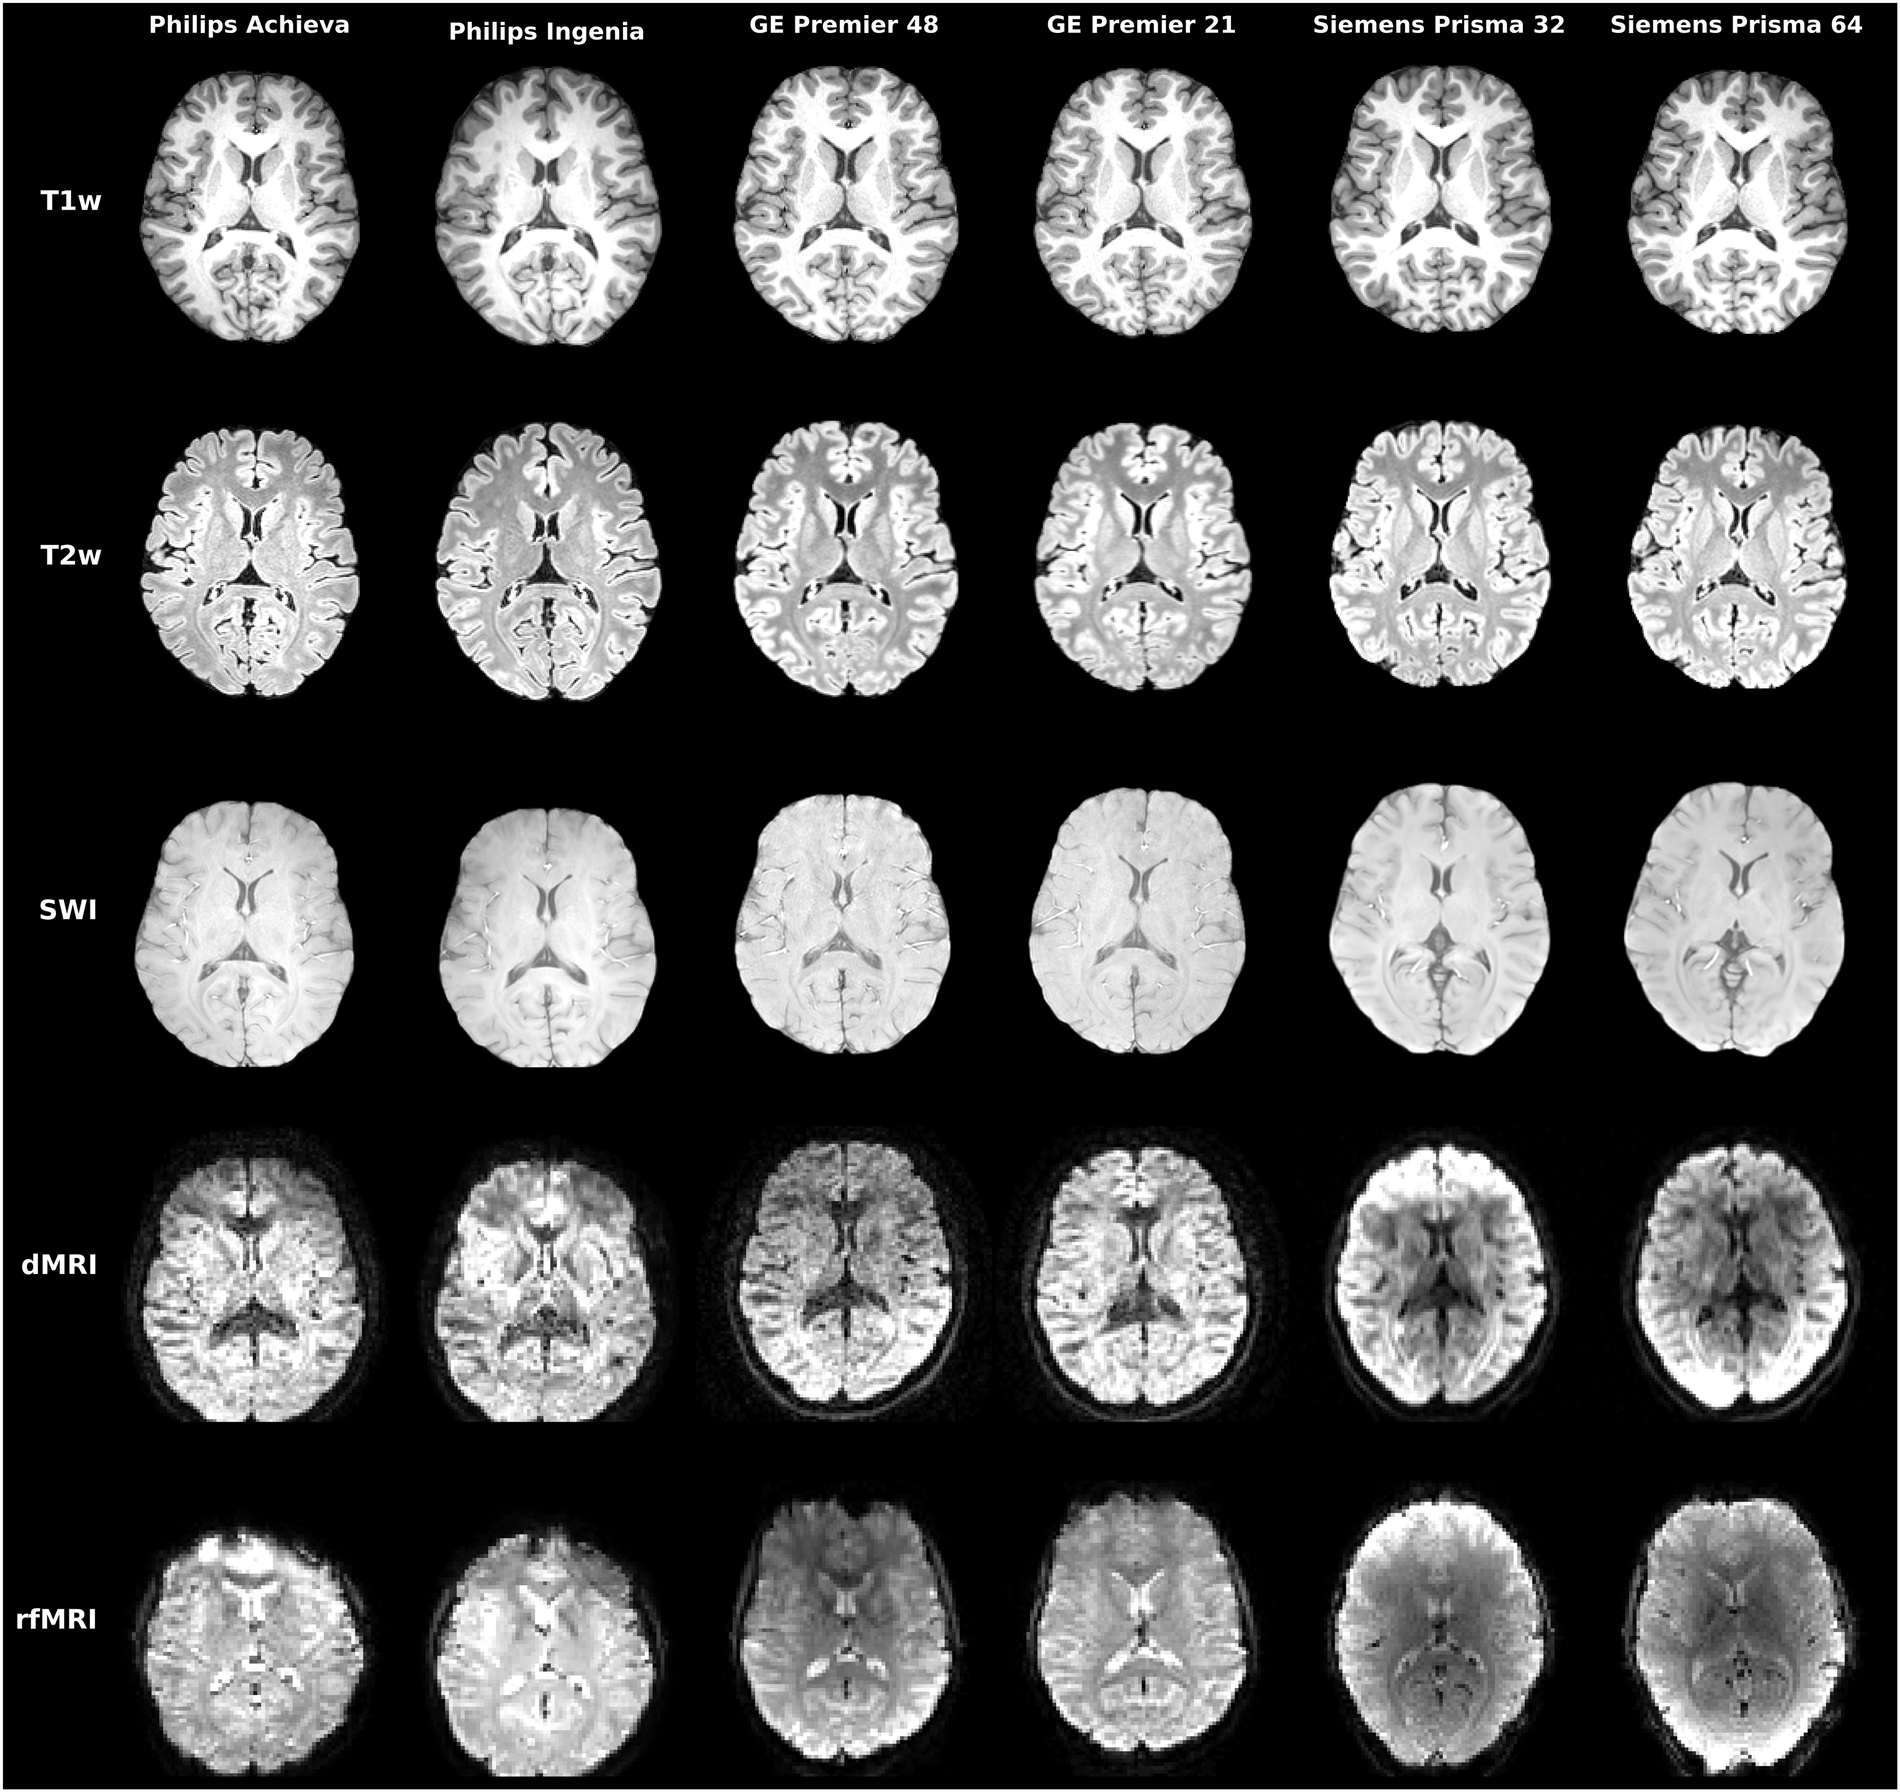

Taking ON-Harmony [125] as an example, 20 healthy volunteers were scanned using five imaging modalities across six scanners from different vendors and models. These modalities included structural imaging (T1-weighted, T2-weighted, and susceptibility-weighted imaging) as well as functional imaging (diffusion MRI and resting-state functional MRI). As shown in Figure 6, a clear observation is that functional modalities exhibit substantially greater inter-scanner variability than structural ones. This discrepancy arises not only from differences in reconstruction and post-processing pipelines across scanners, but also from the fact that both dMRI and fMRI typically rely on fast echo-planar imaging sequences for data acquisition, which are more susceptible to imperfections such as field inhomogeneities and noise.

Refer to caption

Figure 6: Representative examples of all modalities for a single participant data across all scanners from ON-Harmony dataset [125].